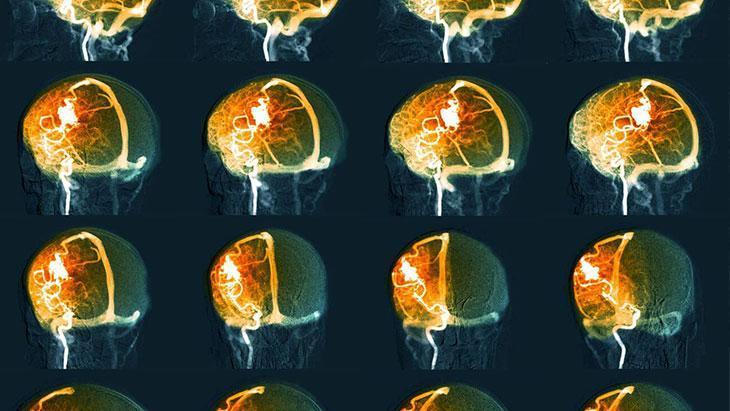

Op.Dr. Kınalı, beyin kanamasının nasıl tedavi edildiğiyle ilgili şunları söyledi: "Başvuru yapan hastanın detaylı ve hızlı muayenesinden sonra hekimin kararına göre beyin kanaması düşünülen hastalarda acil şartlarda çekilecek olan beyin tomografisinin en hızlı tanı yöntemi olduğu, buna ek olarak gerek duyulması halinde etkenin belirlenmesi için MR veya anjio yapılmasının uygun olacağını belirtti. Beyin kanamasında tanıda altın standart ise kasıktan anjiyo işleminin uygulanmasıdır."

Tomografi ya da anjiyo ile kanayan bölge tespit ediliyor

Tomografi ya da kasıktan girilerek yapılan anjiyo ile beyin kanamasının olduğu bölgenin tespit edildiğini ifade eden Op.Dr. Kınalı, “Ölümcül acil cerrahi gereksinimi olmayan ve ya cerrahi sonrası özel durumlarda tüm damarların görüntülenmesinde kullanılan Dijital Substraksiyon Anjiyografi kullanılarak herhangi bir baloncuk ya da damar yumağına bağlı bir kanama olup olmadığı tespit ediliyor.